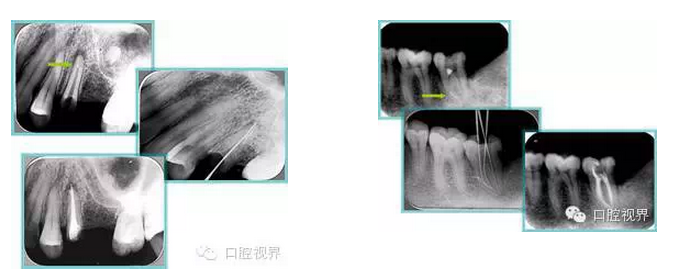

常見(jiàn)有修復(fù)性鈣化和增齡性鈣化。下面為根管鈣化 X 線片。

解決方法: ( 1 )清楚根管系統(tǒng)解剖形態(tài)。 ( 2 )安全頭的金剛砂鉆開(kāi)髓,低速球鉆磨除鈣化牙本( ET20 ,ET40 ,DG-16 )。 ( 3 )徹底去除髓腔周壁的牙本質(zhì)齡。 ( 4 )借助化學(xué)性藥劑,如EDTA 等。

( 5 )初銼選用 8# 或 10#K 銼,平衡力法探察到工作長(zhǎng)度 , H銼上下提拉法使根管擴(kuò)大,提高工作效率

右圖及下圖為器械折斷的 X 線片。箭頭處示折斷器械。

解決方法: ( 1 )取出。 ( 2 )通過(guò)。 ( 3 )重新確定工作長(zhǎng)度,充填。 ( 4 )根尖手術(shù)。